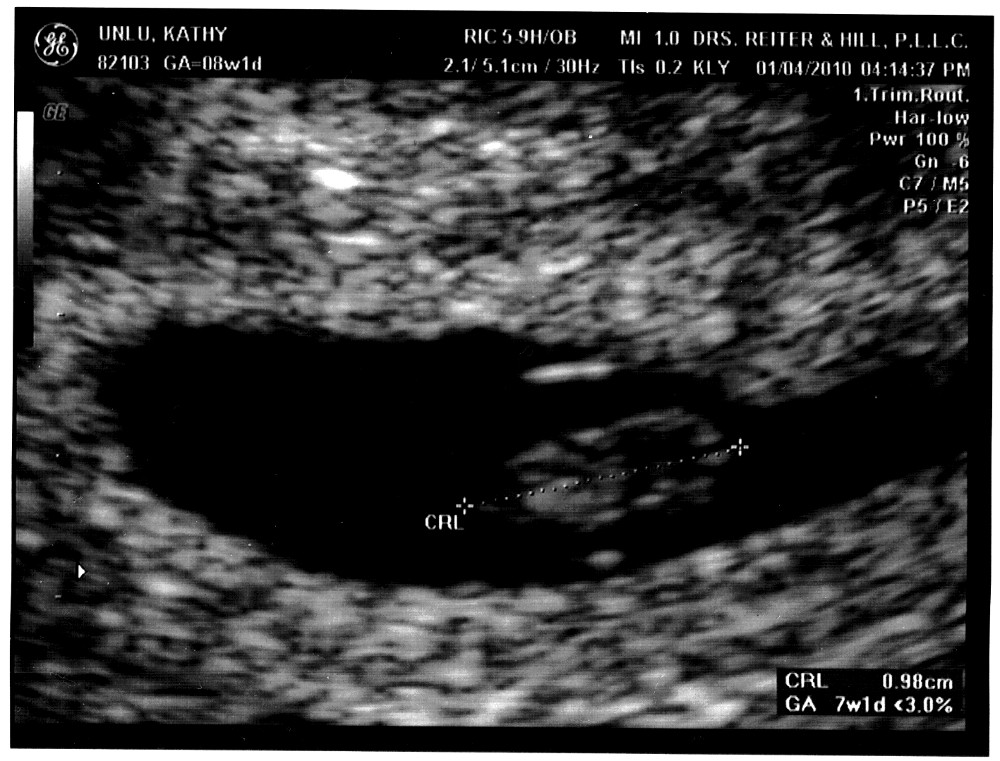

I loved you when I first laid eyes on you. I know for a fact that you could not have known that anyone was watching you at that moment (because you did not even have eyes yet), but yet there you were, strecthing out your full length (of 1 cm) as if you somehow sensed it.

I knew that you were all right even before the ultrasound lady told us everything looked normal for a seven-week old embryo and gave us this snapshot. I knew with the inexplicable feeling that parents know, that feeling that my parents have often talked about and have told me that I would not understand until I too became a parent. And they were right - I never understood. Until a few weeks ago that is.

I knew that I loved you then, even though you were a total stranger, just a tiny bead in your mother's womb, a mass of cells, but one which even at that time had a heartbeat. It was fantastic to hear the sound, the thump-thump-thump of it coming through the microphone. The sound was even more fantastic because it mirrored mine.